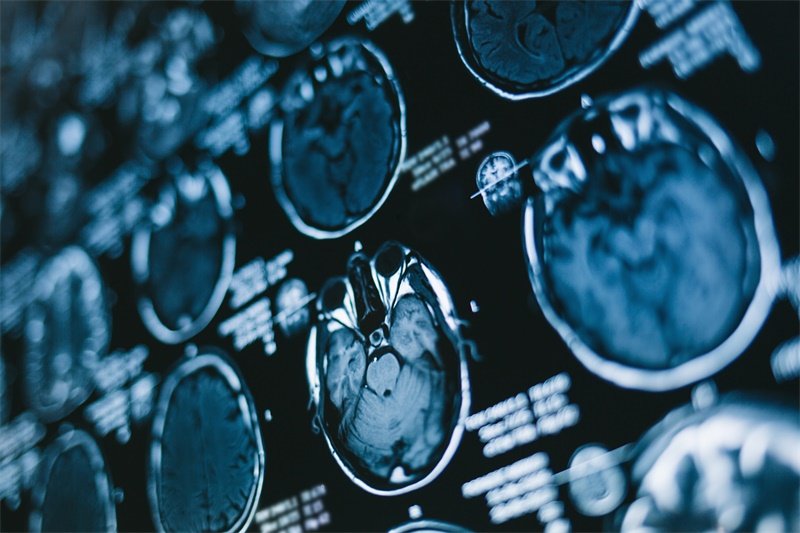

右侧丘脑作为感觉信息传导的“核心中继站”,协调着痛温觉、本体感觉和情感认知等多重功能。当这个深部脑区出现占位性病变时,症状往往复杂隐匿——从难以解释的偏身灼痛到突发性意识波动,从体温调节失常到情感认知障碍。尤其值得注意的是,丘脑病变中恶性肿瘤占比高达60%以上,远高于其他脑区病变的恶性比例。中国脑肿瘤登记中心2024年数据显示,右侧丘脑肿瘤患者5年生存率不足40%,其中血管性病变的预后显著优于肿瘤性病变。这些数据提醒我们,精准识别病因与科学干预对改善预后至关重要。

右侧丘脑占位性病变并非单一疾病,而是涵盖肿瘤性、血管性、炎症性及代谢性病理改变的统称。该区域作为感觉传导通路的关键节点,病变会同时中断丘脑皮质束与边缘系统环路,导致独特的“感觉-情感分离综合征”。

肺癌脑转移占比超55%,乳腺癌转移约占25%。转移灶多位于丘脑-基底节区血供分水岭,磁敏感加权成像(SWI)可显示特征性“爆米花样”出血信号。